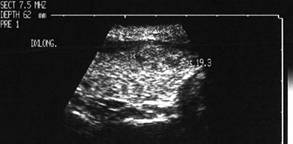

Lob drept , proiectie trasversala si longitudinala.

Femeie 19 ani. Leziune marcant hipoecogen cu intarire posterioara, de 16x20x26mm (4 cc) in lobul drept.

Examen citologic: macrofagi, fara tireocite.